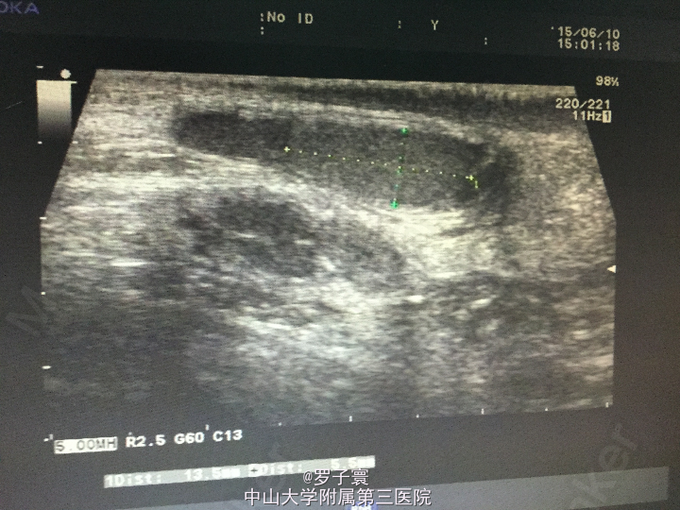

查体:阴茎呈男童外观,包茎,左侧阴囊空虚,未触及任何内容物,左侧腹股沟可触及睾丸样团块,质地软,大小1.4*0.6cm,无触痛,无粘连,站立活动后右侧阴囊可触及质软肿物,透过试验阳性,可扪及右侧睾丸,大小约1.5*0.8cm,触诊质地软,表面光滑,无硬结,无压痛,附睾、精索触诊不满意。生殖系彩超(我院,2015-06-10):双侧阴囊内睾丸缺如;双侧腹股沟部隐睾(左侧活动度大);右侧睾丸鞘膜积液。